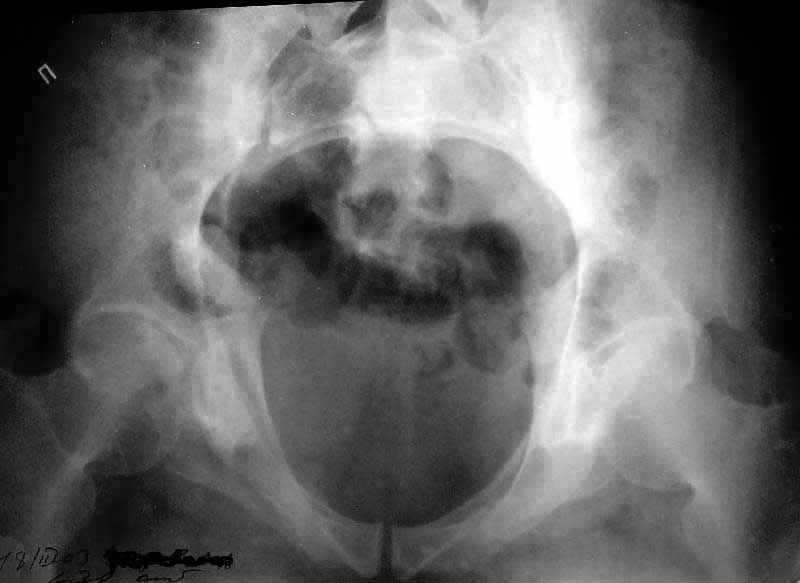

Attached. I may upload the one with larger resolution.

Based on the CT images you provided, he appears to have a nonunion of the the right ischium, which would explain his symptoms. General principles of treatment of hypertrophic (which this appears to be) nonunions suggest rigid fixation, but I'm not sure what the best approach would be. Could get a lag screw across the fracture through a Kocher-Langenbeck approach or plate osteosynthesis through direct ischial approach, but perhaps Chip, Adam or someone with more pelvic fracture experience could enlighten us all.

I think the cuts in question (albeit small) are on the right of the bottom row of the CT scan

I think this is just a pelvic ring disruption that has gone on to a non-union. The arrow is pointing to the inferior ramus non-union, and the sup ramus is a high "root" fracture, right near the pecten. The sup ramus fracture enters the tab - you could call it an acetabular fracture - but down here in Dallas we treat these acutely as stable pelvic ring injuries. The fracture in the anterior portion of the acetabulum is so low it doesn't seem to cause much trouble.

His R sacroiliac joint is opened anteriorly a little bit - the "unreduced posterior lesion" Alex mentioned in his first post. My earlier post about plating, bone grafting, etc., is all wrong.

What you have is a pelvic fracture that hasn't healed after 4 months or so, with a minimal deformity.

I think what I would offer the guy is a percutaneous iliosacral screw to stabilize and improve the SI joint alignment, coupled with a perc anterior column screw to stabilize the high ramus fx. These screws aren't easy to place, and have a host of potential problems and complications. But, I think they would work.

Here is a link to "full-size" CT image (scanned with 300 dpi resolution to 2776x1832 pixels). Thanks for advice.